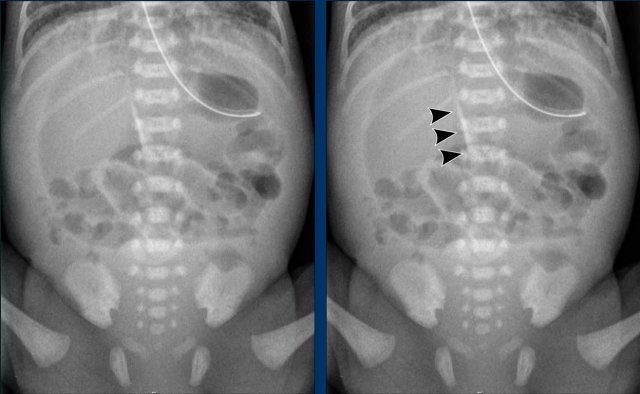

Bowel distribution

Distribution of air should be assessed, as regional paucities of gas may represent diseased bowel.

As the right lower quadrant is the site most commonly affected by disease, this is also the area, that will most often show absence of bowel gas.

Another important sign is the persistent loop.

Images

Abdominal radiographs demonstrating dilated bowel loops and asymmetric distribution of air with paucity in the right lower quadrant.